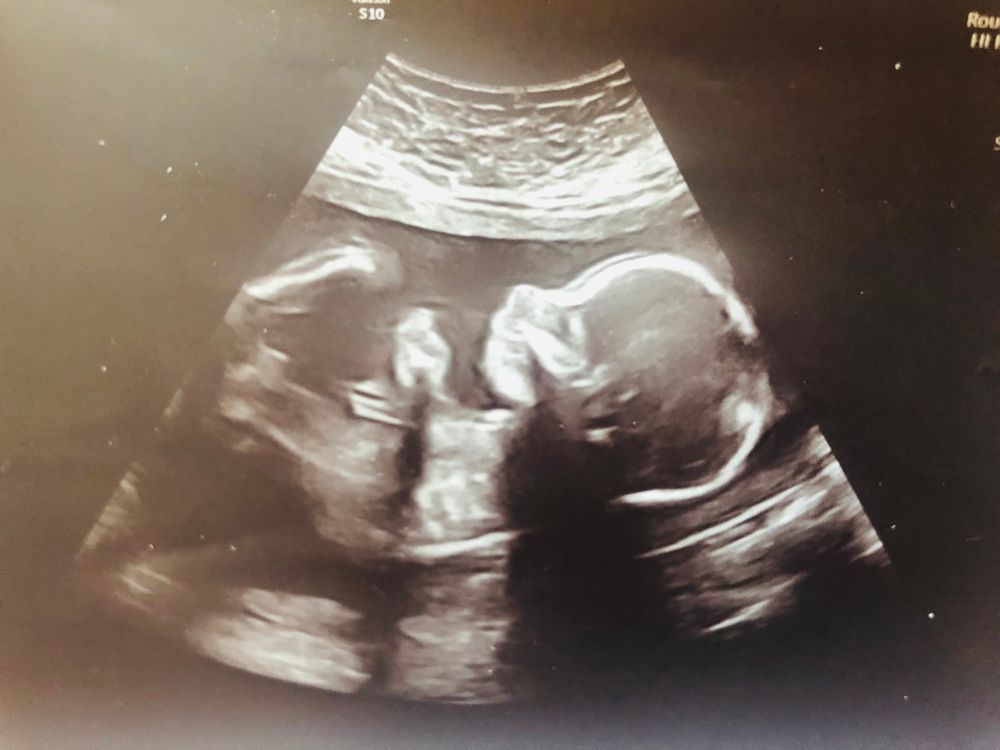

40 роддом Москва. Второй скрининг.

Я тоже в 40 роддом на скрининг ходила два раза. Сейчас третий скрининг отменили, только по показаниям. Врачи очень хорошие, отзывчивые, по человечески относятся. На дневном стационаре тоже там была, сдавала анализы, но процедур никаких не назначали. Хотела рожать в этом роддоме, но он на мойке как раз в это время будет.